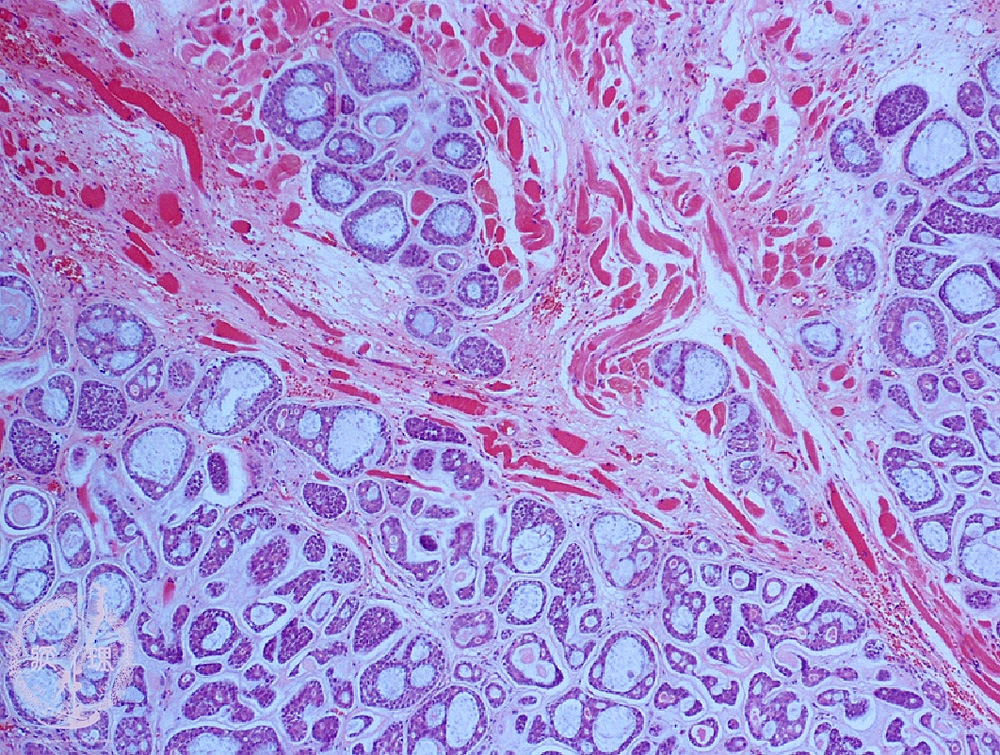

ミクロ像(HE弱拡大):多数の篩状、管状胞巣が筋組織内(*)に浸潤性に増殖している。